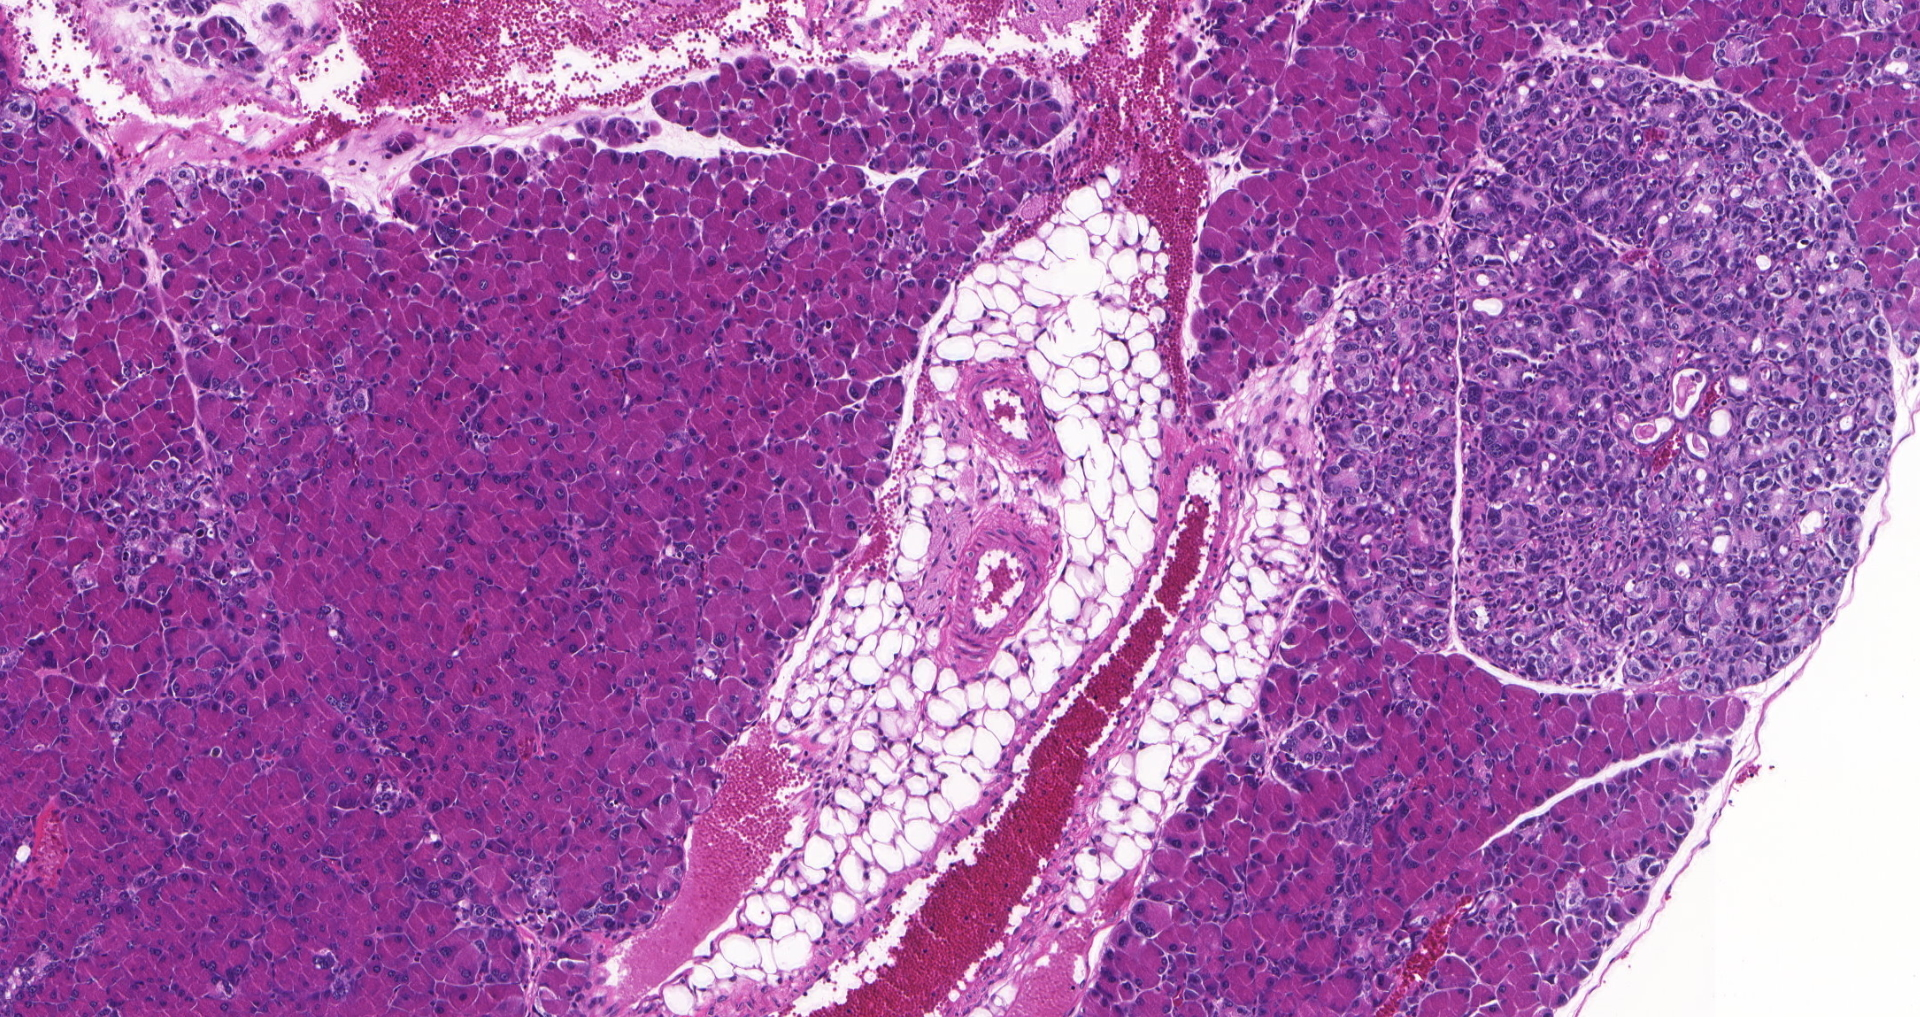

Studying how metabolism controls cancer initiation

The lab aims to uncover how metabolic changes control the earliest steps of cancer formation, with the long-term goal of identifying new strategies for cancer detection and prevention.